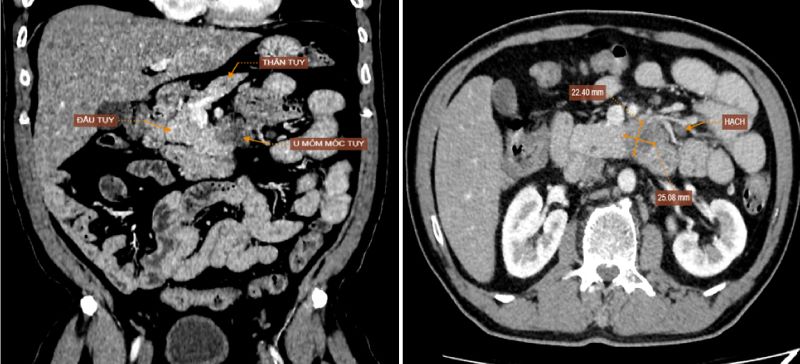

Kết quả nội soi không ghi nhận bất thường, tuy nhiên hình ảnh CT cho thấy khối u vùng mỏm móc đầu tụy có dấu hiệu xâm lấn động mạch mạc treo tràng trên và tá tràng. Đồng thời phát hiện thêm tổn thương đa ổ ở gan, hạch ổ bụng và nốt đặc ở thùy dưới phổi phải – nghi ngờ di căn xa. Kết quả sinh thiết sau đó xác nhận bệnh nhân mắc u:ng th:ư biểu mô tuyến tụy giai đoạn T4N2M1 (giai đoạn cuối). Bệnh nhân được chuyển sang cơ sở chuyên khoa ung bướu để tiếp tục điều trị.

Hình ảnh chụp cắt lớp vi tính ổ bụng phát hiện khối u vùng mỏm móc đầu tụy.